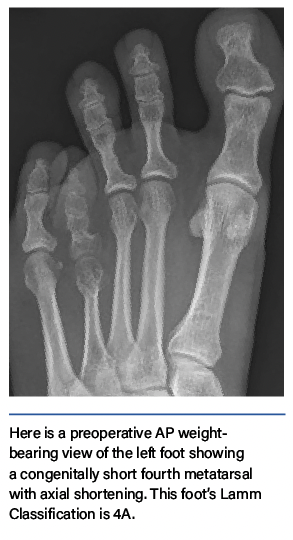

Brachymetatarsia deformities range from purely short metatarsals to irregularities of specific regions of the bone, including the shaft, head, and joint. The Lamm Classification is based on the normal foot radiographic measurements and angles.14

- Type A (axial distance deficiency) includes metatarsals that are normal in all respects except for their shortened length.

In addition to the A, B, and C types, the classification system uses one number ranging from 1–5 to indicate which metatarsal is short or hypoplastic.5 Therefore, if a patient has a short fourth metatarsal, bowing of the metatarsal shaft, and an incongruent MTPJ, this patient would be classified as a 4ABC.